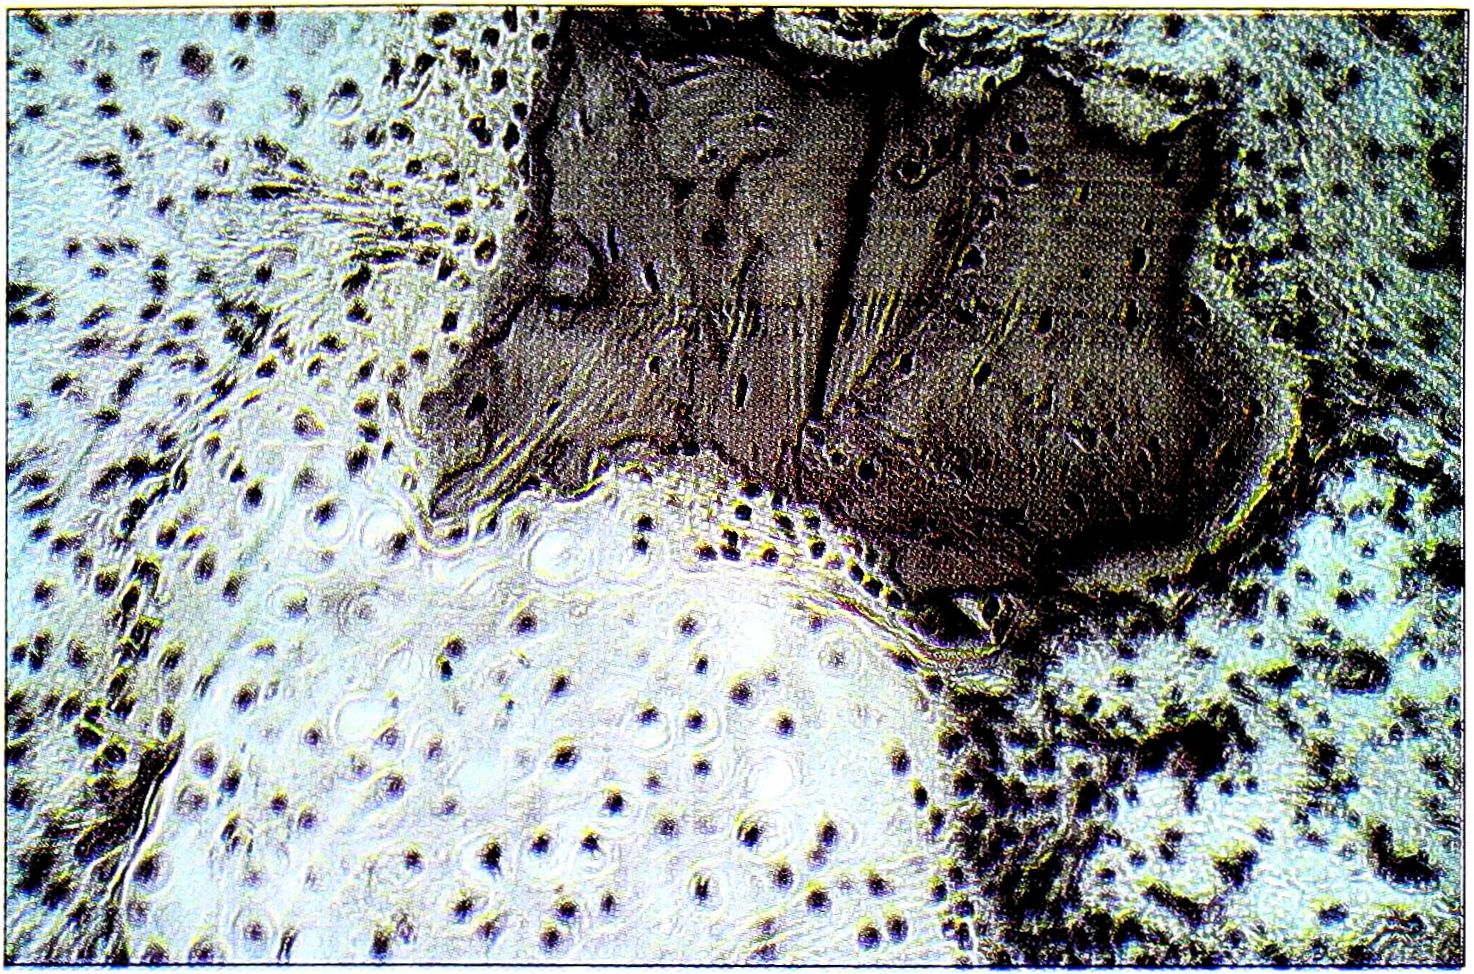

Патогистологическое исследование выявило при всех формах коксартроза III-IV стадии выраженные дегенеративные изменения суставного хряща — разволокнение и разрыхление всех его слоев, формирование глубоких трещин и фрагментацию, истончение и локальное разрушение, вплоть до образования костных «шлифов». У значительной части больных в субхондральной зоне обнаруживались псевдокисты и истинные кисты. Псевдокисты определялись на месте некротизированных костных трабекул и элементов костного мозга, замещавшихся соединительной тканью различной степени зрелости. В псевдокистах были видны элементы дистрофически-измененных и некротизированных костных трабекул, признаки патологического обызвествления, гиалинизации коллагеновых волокон, а также локальных некрозов соединительной ткани. В некоторых случаях встречались участки хондроидной ткани и гиалинового хряща, расположенные отдельными островками или примыкающие к дистрофически-измененным костным трабекулам (рис. 3), что объяснялось переломами трабекул и их микроподвижностью. Часто определялись выраженные клеточные инфильтраты, представленные полиморфноядерными лейкоцитами, лимфоцитами, гистиоцитами и плазматическими клетками, указывающие на наличие хронического воспалительного процесса. В большинстве случаев в разных участках псевдокист встречались отдельные остеоидные или относительно незрелые костные балочки, что свидетельствовало о процессах реактивного костеобразования.

Рис. 3. Гистологическая картина при диспластическом коксартрозе с кистовидной перестройкой: к остаткам дистрофически-измененной костной трабекулы прилежит гиалиновый хрящ (окраска гематоксилином и эозином, ув. 160).